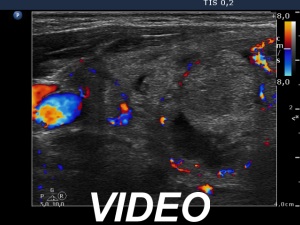

Ultrasonography. Both lobes were composed of multiple nodules of different echogenicities including cystic ones and a large hyperechogenic lesion in the lower part of the right lobe. Except for a moderately hypoechogenic nodule in the dorsal part of the left lobe, the lesions had no oncological significance. The extranodular part was echonormal.